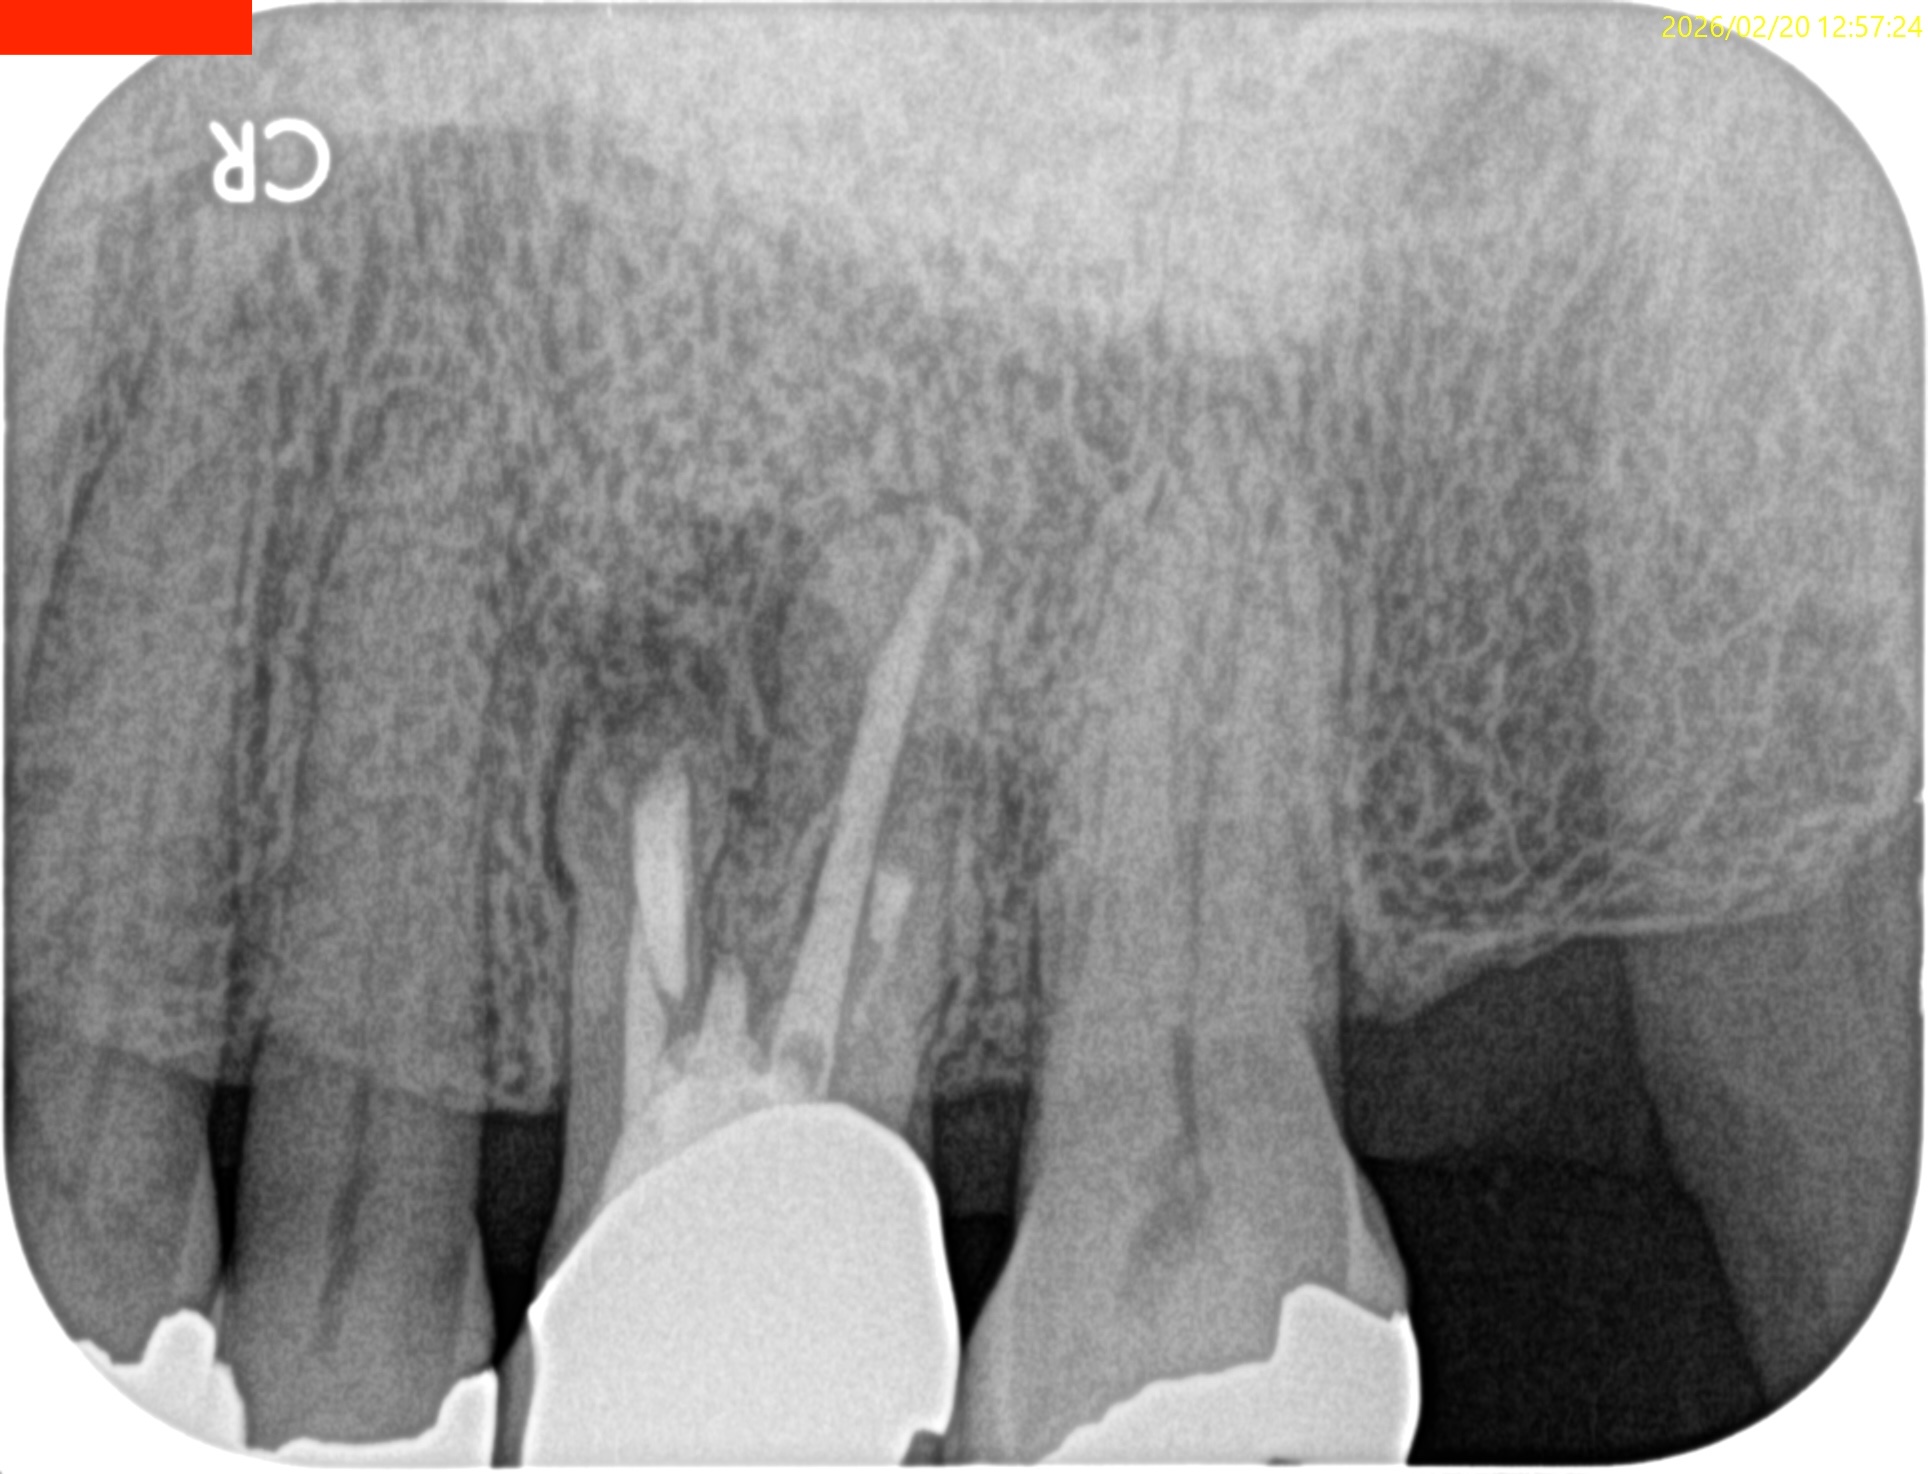

後日、抜糸に来られた。

#14 Suture removal(2026.2.20)

次回は半年後である。